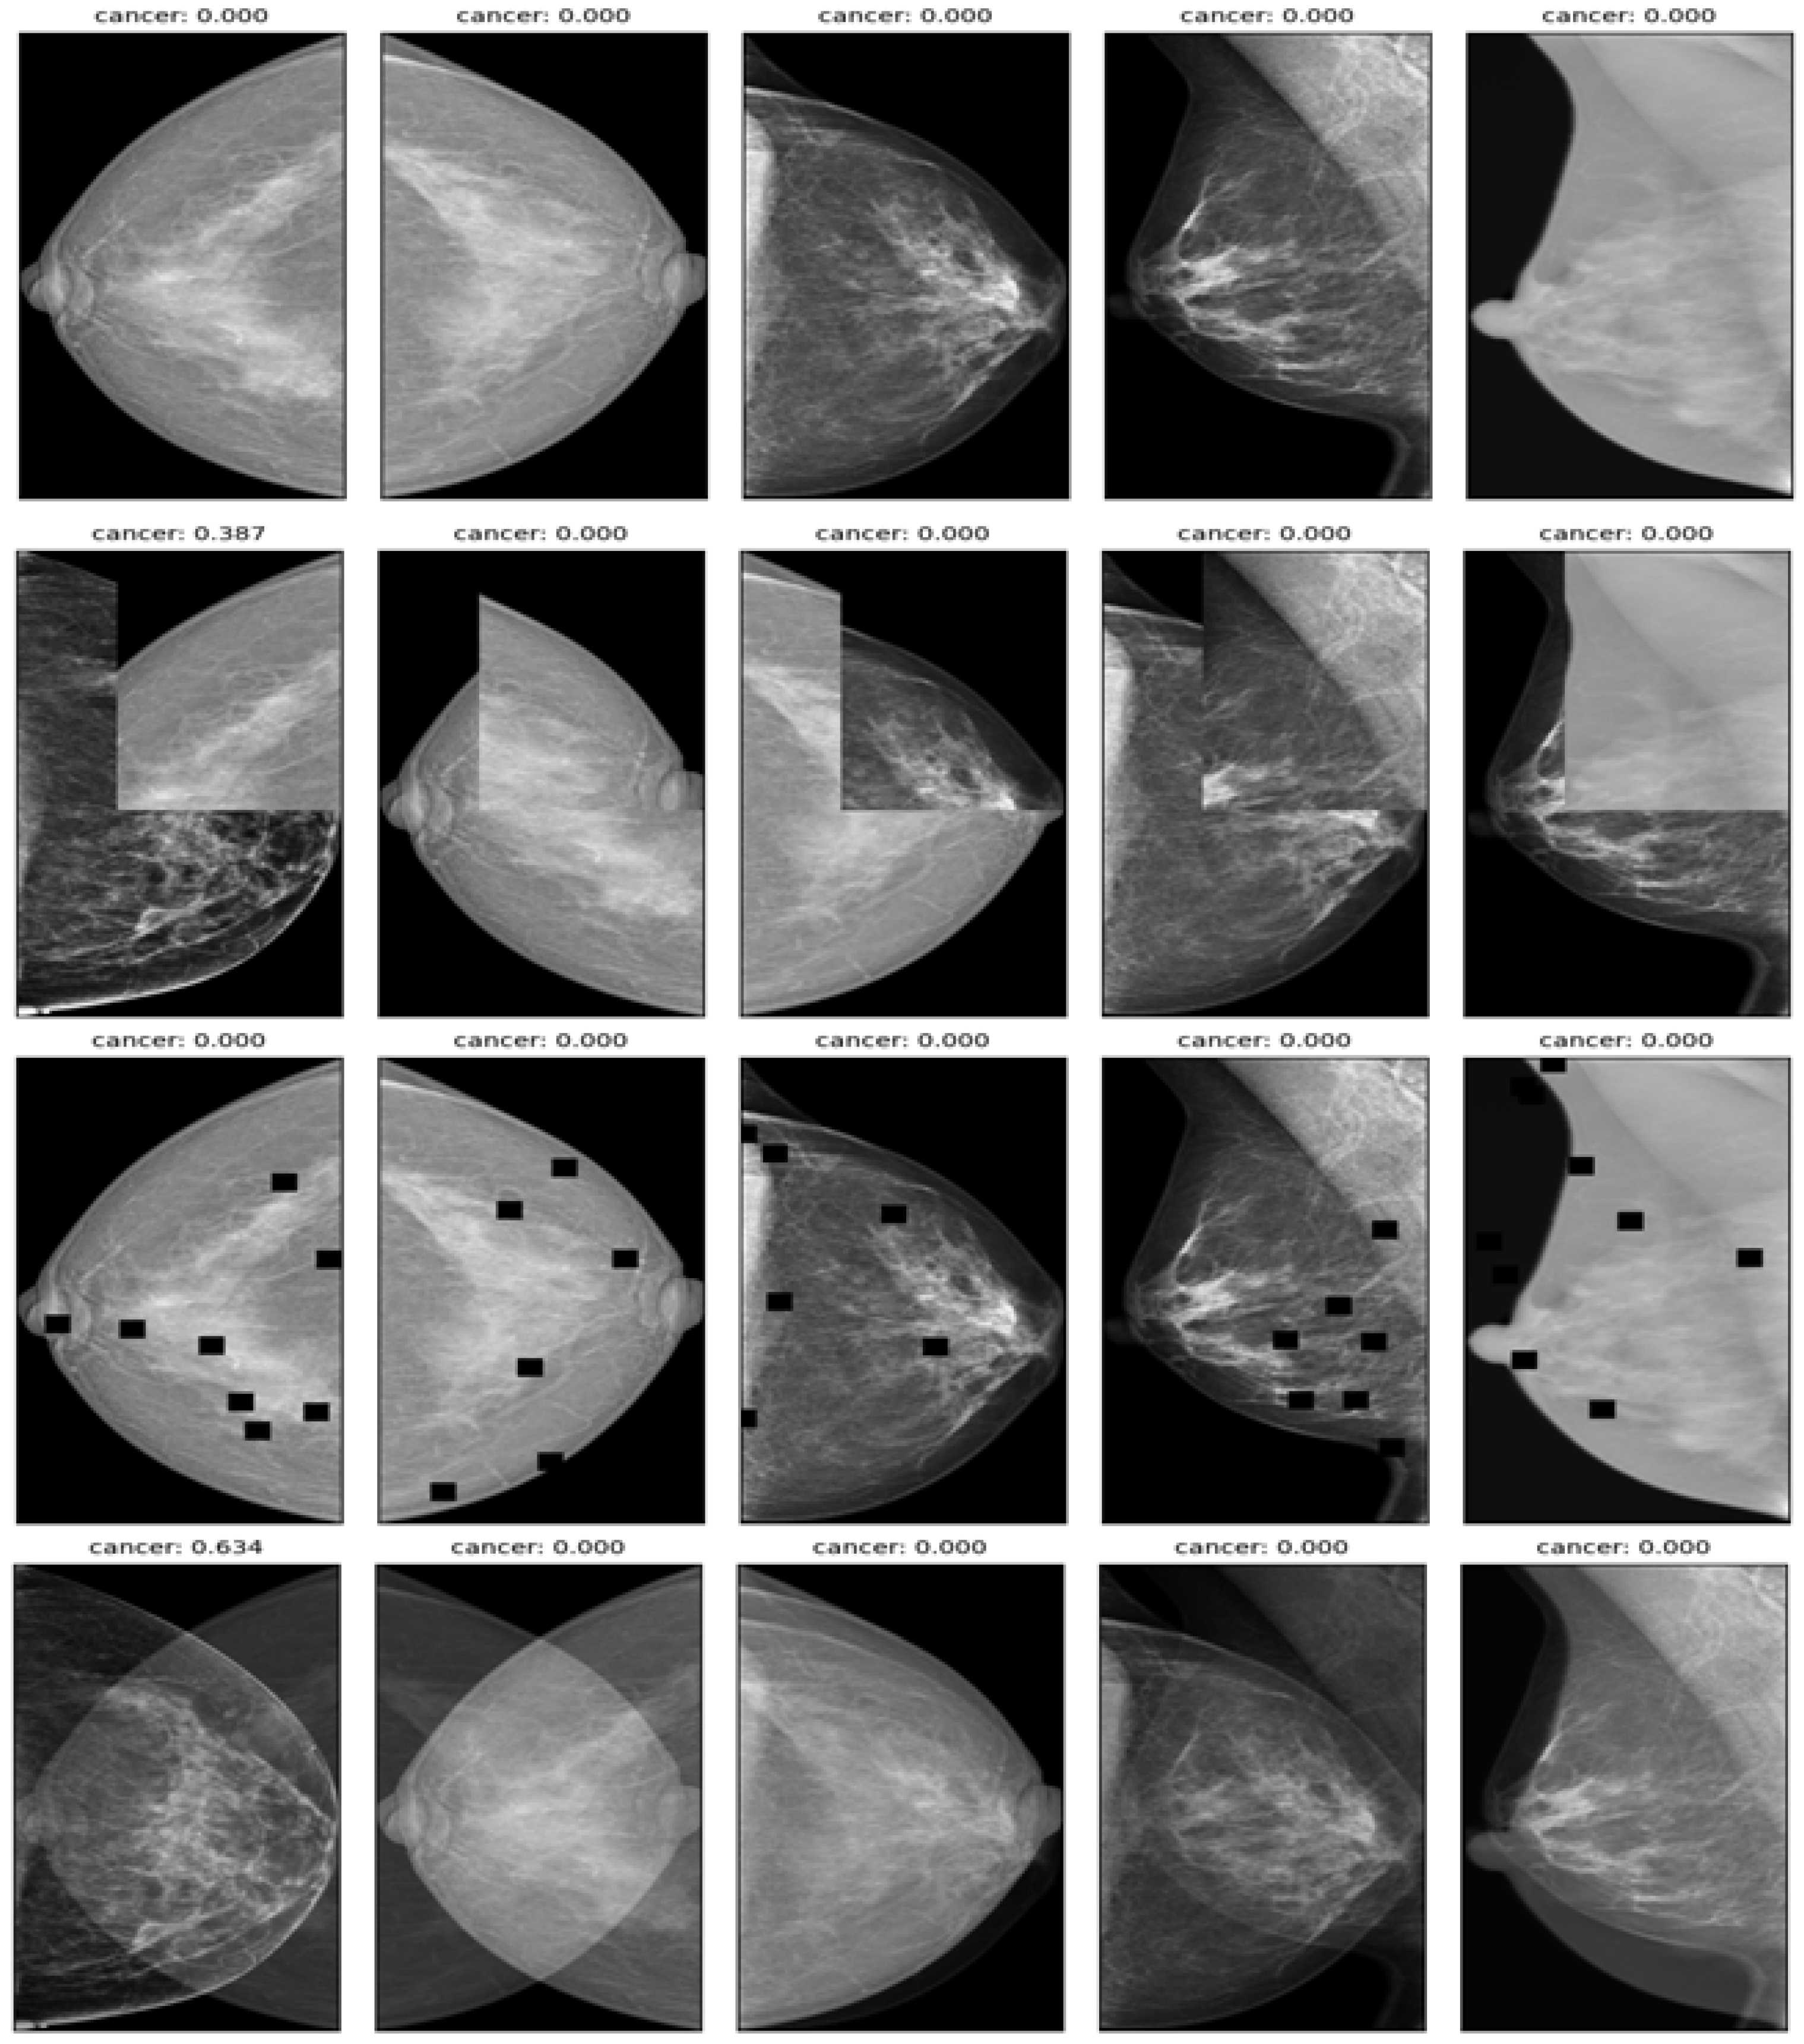

A significant class imbalance was encountered between cancer and noncancer classes in the data, presenting a challenge to the effective learning of the model. Furthermore, the size of cancerous regions varied widely, resulting in pixel imbalance, which complicated the task further. Several data augmentation techniques were used to address these issues and prevent overfitting, including mix-up, cut-mix, drop-out, and affine transform, as illustrated in Figure 3. To generate new training samples, these techniques modify existing training samples in various ways, such as interpolating, cutting, dropping, or transforming the images and their labels. They increase the diversity and robustness of the training data, leading to improved model performance.

Figure 3.

Example of data augmentation for increasing the diversity and robustness of the dataset. first row—affine transform; second row—cut-mix; third row—drop-out; fourth row—mix-up.

- Mix up: A technique that generates new training samples by linearly interpolating between two images and their labels. This technique can produce high-quality inter-class examples that prevent the model from memorizing the training distribution and improve its generalization ability.

- Cut-mix: A technique that generates new training samples by randomly cutting out patches from two images, pasting them together, and assigning the labels according to the area ratio of the patches. This technique can also produce interclass examples that enhance the model’s robustness to occlusion and localization errors.

- Drop-out: A technique randomly drops out units in a neural network layer during training to prevent overfitting. This technique can decrease the co-adaptation of features and increase the diversity of feature representations.

- Affine transform: A technique that applies geometric transformations such as scaling, rotation, translation, and shearing to the images. This technique can increase the invariance of the model to geometric variations and improve its performance on unseen images.